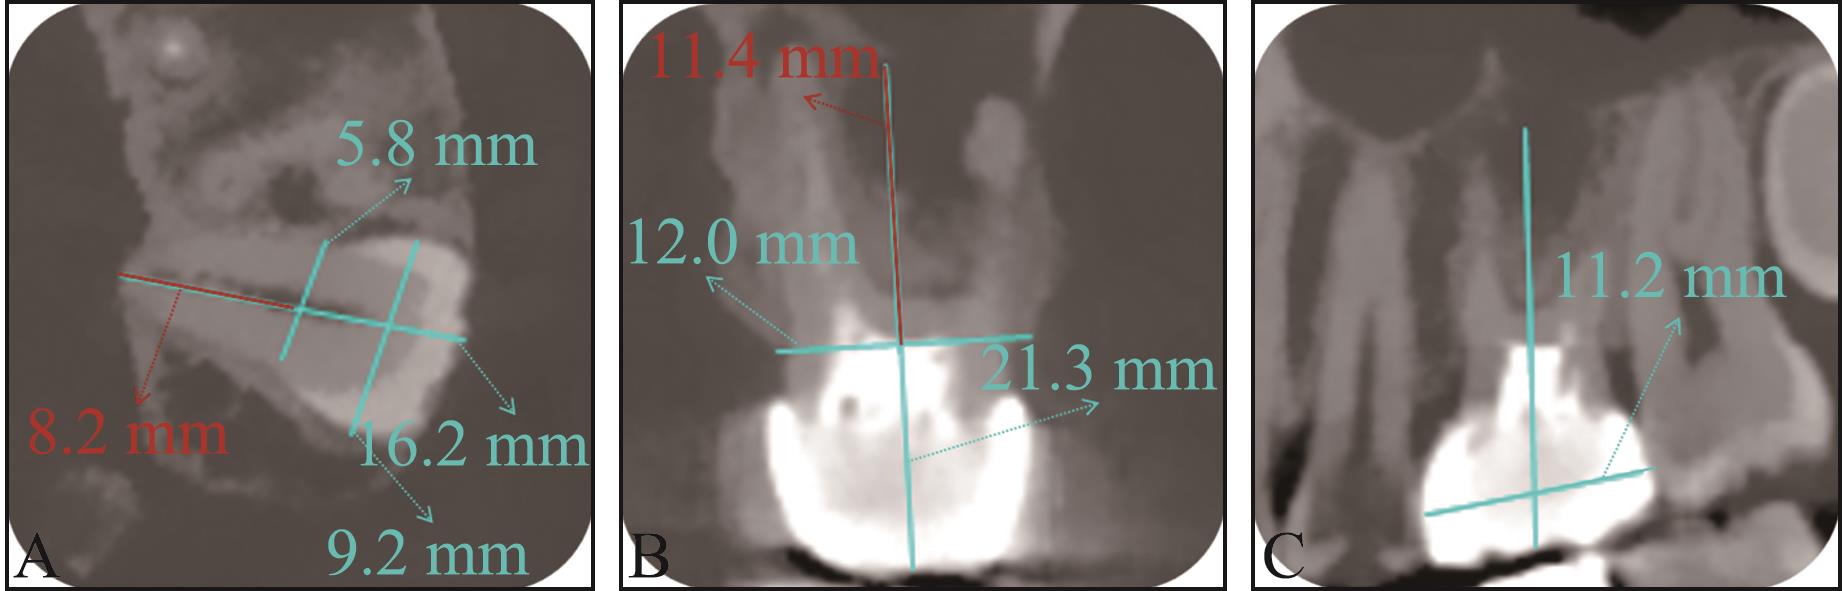

Zhang H, Cai M, Liu Z, et al. Combined application of virtual simulation technology and 3-dimensional-printed computer-aided rapid prototyping in autotransplantation of a mature third molar[J]. Medicina (Kaunas), 2022, 58(7): 953.

|